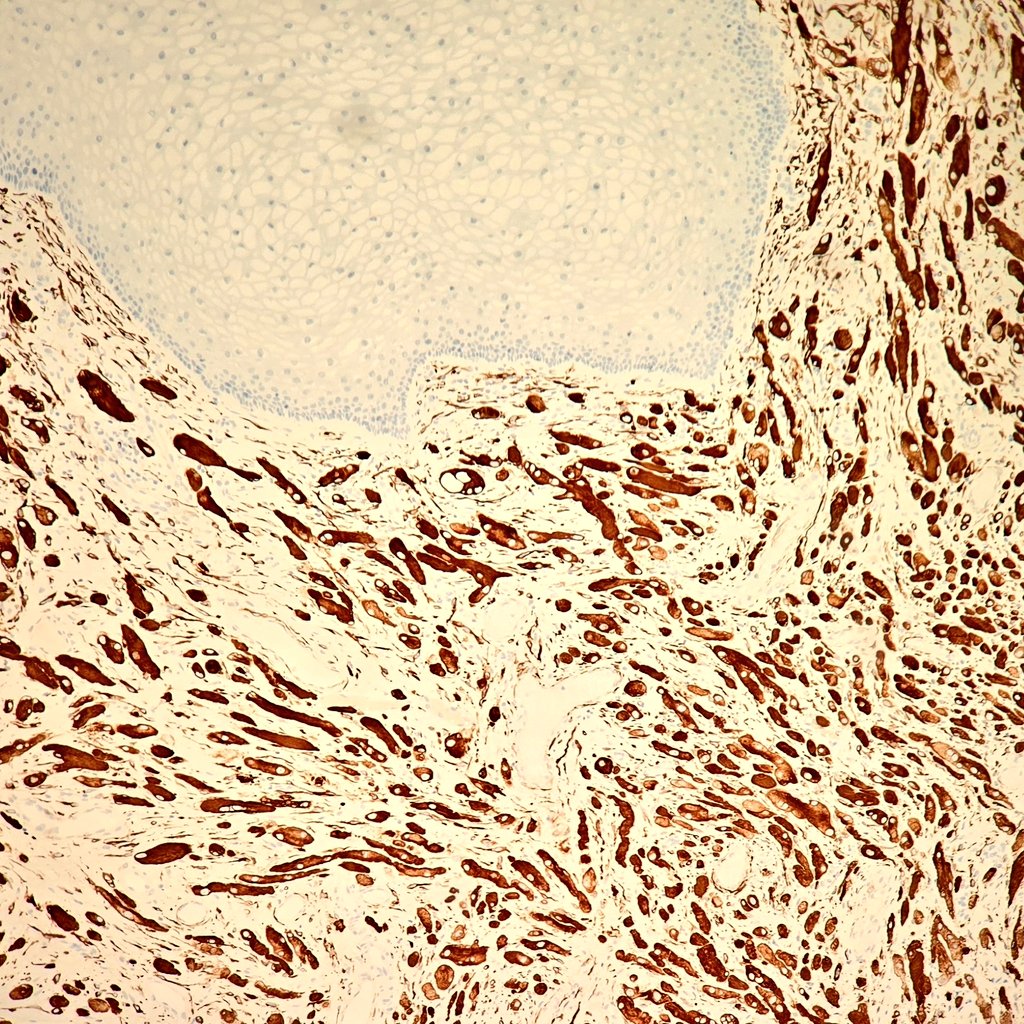

✨️Glomus tumor✨️ ▫️Well circumscribed mass composed of 3 components: glomus cells,vasculature and smooth muscle cell ▫️vessels surrounded by collars of uniform glomus cells forming nests & sheets ▫️+ for SMA,MSA,calponin, hcaldesmon,collagen type IV - for cytokeratin & S100